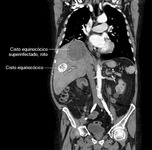

Abscesso hepático: tomografia computadorizada (TC) mostrando um cisto equinocócico rompido e infectado de 8 cm por 8 cm e um cisto equinocócico de 4 cm por 4 cm em um homem de 69 anos de idade, que apresentou hipotensão e dor torácica com irradiação para a região epigástrica

Do acervo de imagens radiológicas do Massachusetts General Hospital (MGH)